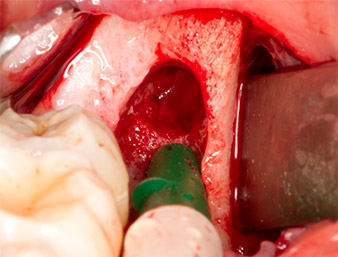

Pour obtenir un matériau autogène en vue du traitement ultérieur de la plaie, des fragments osseux sains sont collectés autour du reste radiculaire à l'aide d’un insert piézochirurgical (Piezomed B5) (Fig. 5).

Le tissu autogène est extrait à l’aide de la section en forme de racloir de la pièce active de l’insert et conservé dans un soluté physiologique isotonique jusqu’à utilisation ultérieure (cf. Fig. 13).

Pour exposer le reste radiculaire en minimisant le traumatisme causé aux tissus, un autre insert est utilisé (Piezomed S2) qui est principalement indiqué pour la préparation de la fenêtre latérale dans les élévations de plancher sinusien. La boule diamantée est également utilisée pour adoucir les bords osseux tranchants (Fig. 6 et 7). Tous les inserts Piezomed sont utilisés avec le paramétrage par défaut automatique, et sans la fonction Booster.